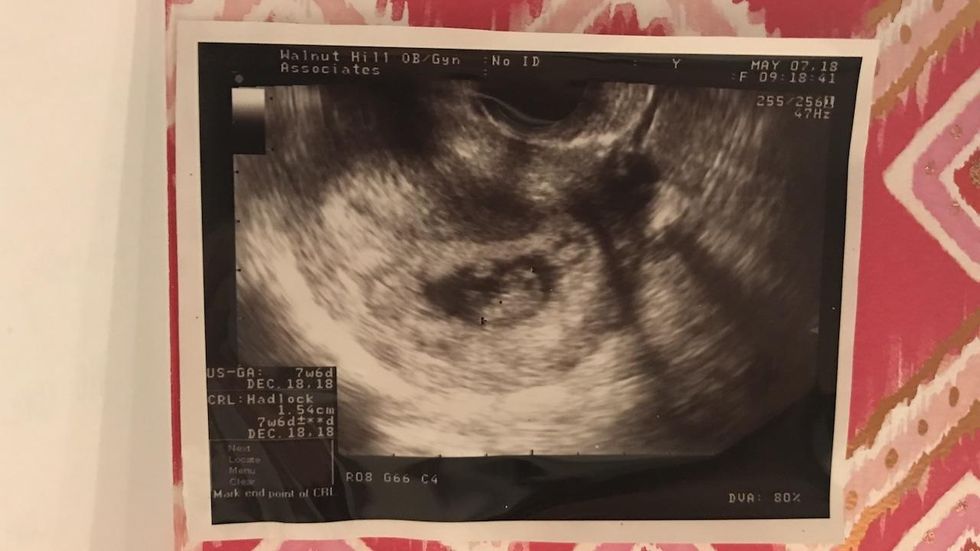

The first sonogram photo of my granddaughter was tucked inside my Mother's Day card. (Jana J. Pruet)

Then, on Mother's Day, Josh and my daughter-in-law Amy surprised me with an amazing gift — the news (and a sonogram picture) of my first grandchild. The excitement of this new little life joining our family sent me instantly over the moon (and into the mall, according to my husband).